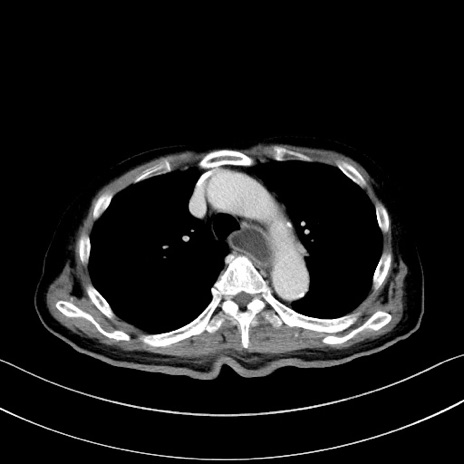

症例28(横断像)

【症例】60歳代男性

【主訴】嘔吐

【現病歴】胃癌にて胃全摘後。食思不振が悪化し、夜中に嘔吐することがある。

【既往歴】胃癌、胃全摘、脾摘、胆摘後

【データ】WBC 5900、CRP 10.56